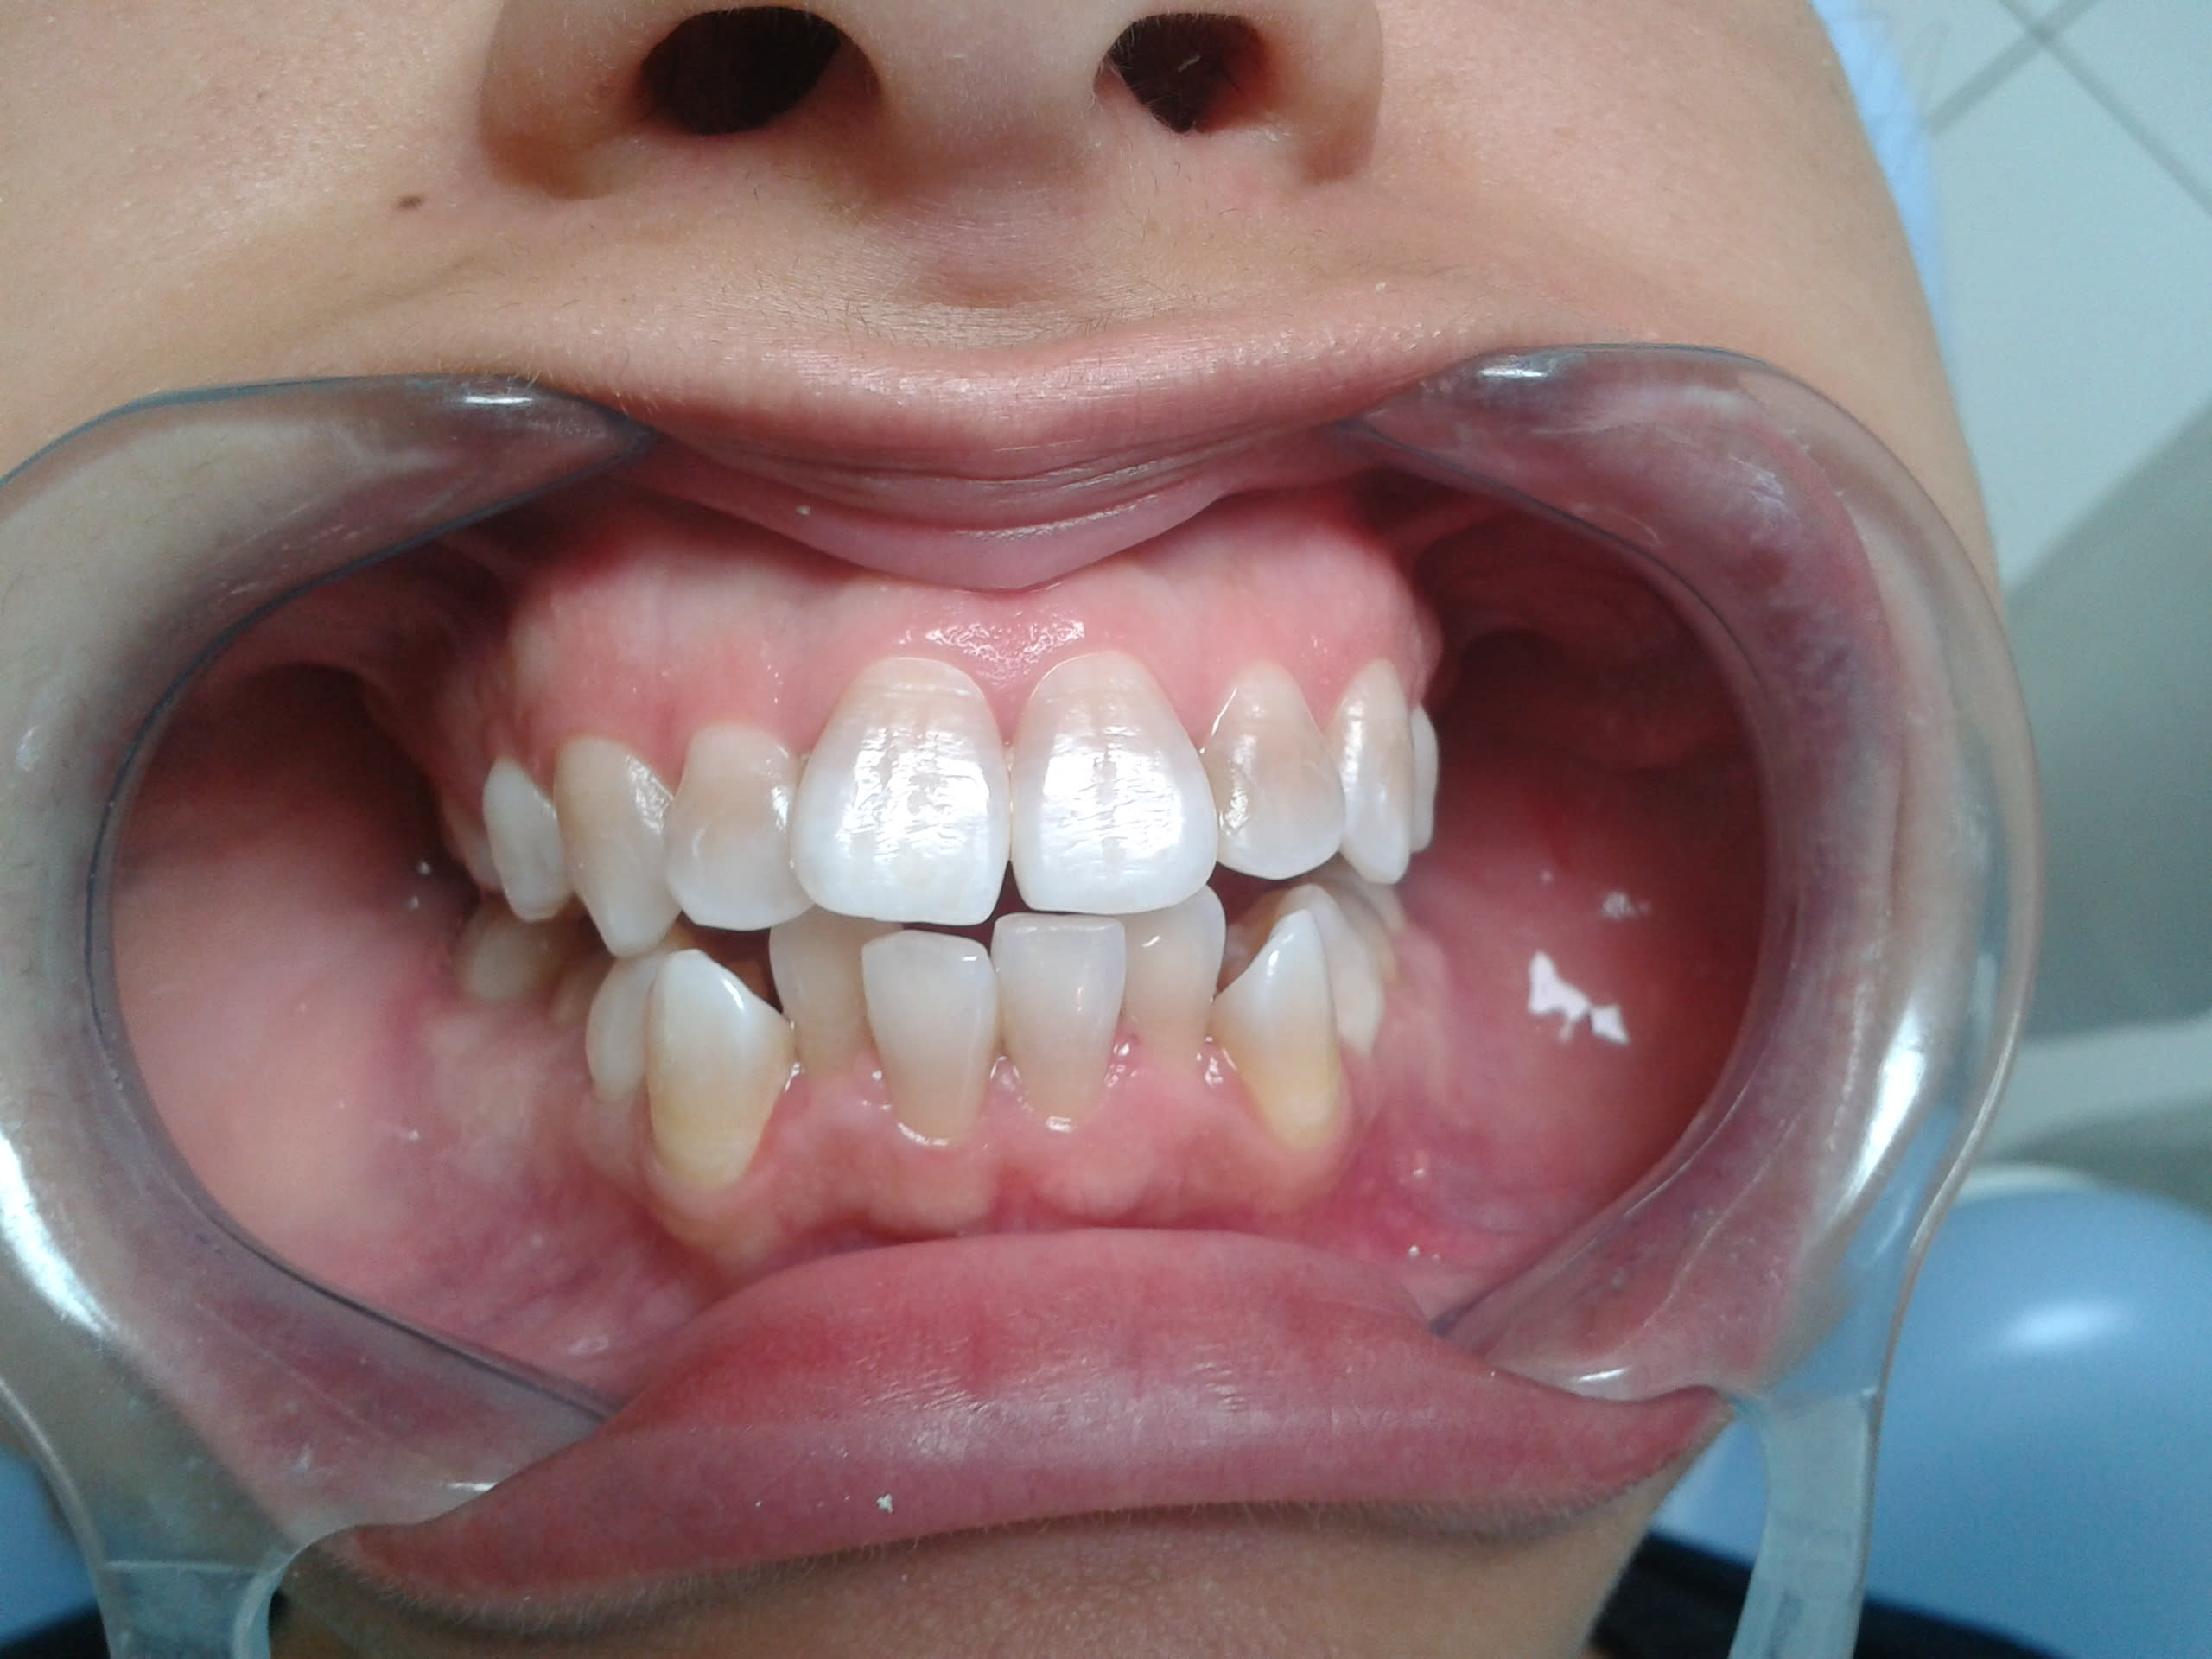

J'ai eu un cas comme ça pour une mamie de 86 ans qui voulait se faire pécho par le père Noël.

Pour les prov, j'ai fait comme Dr_EG a dit.

Les tofs sont pas terribles et le rendu final est mieux mais bon suis pas photographe non plus, à peine dentiste.